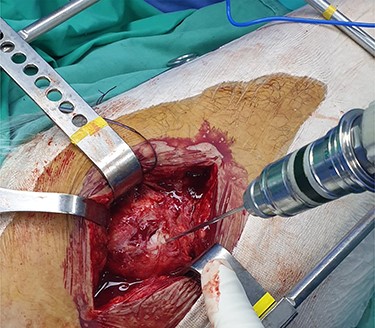

The patient is placed in lateral decubitus position. There is no need of a traction table and fluoroscopy in order to identify the intramedullary canal and the nail inserted. Palpating the prominence of the greater trochanter on the lateral side, an incision is made over it and can be extended distally and proximally. The fasciae latae is carefully incised. The femoral diaphysis and the origin of vastus lateralis are identified. Above the origin of vastus lateralis, k-wires are drilled in order to identify, the anterior and posterior margins of the intramedullary nail in the sagittal plane and mark them and can be left in place (Figs 1 and 2). This is easily performed due to the metal-on-metal effect that is produced during drilling (Fig. 3). Knowing the anterior (point A) and posterior (point P) margins of the intramedullary nail, multiple drillings are performed proximally and perpendicular to the median of the (AP) side of the formed triangle (TAP). The drilling point where no metal-on-metal effect is produced corresponds to the proximal endpoint of the intramedullary nail (point T). Those points form a triangle (TAP) on the lateral side of the femur with the top (T) highlighting the endpoint of the intramedullary nail, and the sides the anterior (A) and posterior (P) margins (Fig. 4). Drilling with k-wires also helps us determine the depth of the nail.

Intraoperative image showing the position of a k-wire in order to indentify the anterior margin of the intramedullary nail.